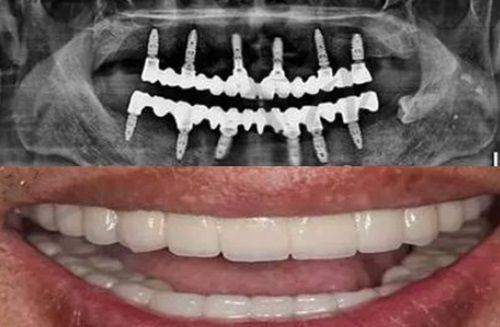

常规项目:微创种植、即刻种植、all-on-4/6半口全口即刻负重种植、骨量不足植骨种植、高龄疑难种植、单颗种植、多颗复杂种植、隐形矫正、金属自锁托槽矫正、陶瓷半隐形矫正、美学修复、牙齿美白、儿童齿科、牙周治疗、牙体牙髓治疗、补牙、补牙、洗牙、牙贴面、烤瓷牙、全瓷牙、根管治疗。